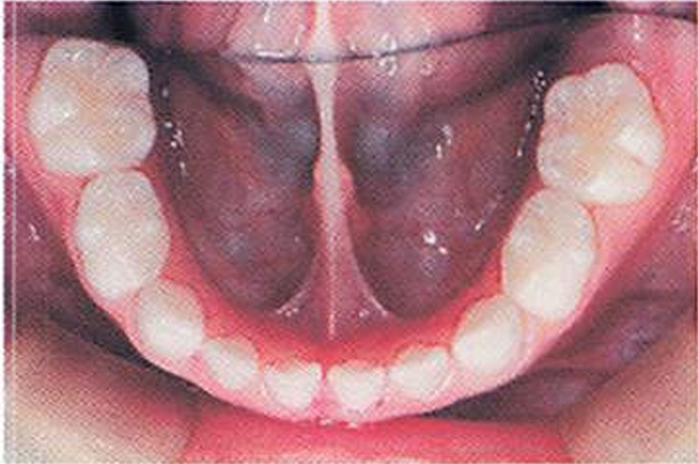

3歳の男児。3歳児歯科健康診査で軟組織異常の指摘を受けて来院した。 初診時の口腔内写真を別に示す。 これによって生じるのはどれか。1つ選べ。

a.開口障害

b.構音障害

c.萌出障害

d.唾液の分泌障害

解答を見る

b